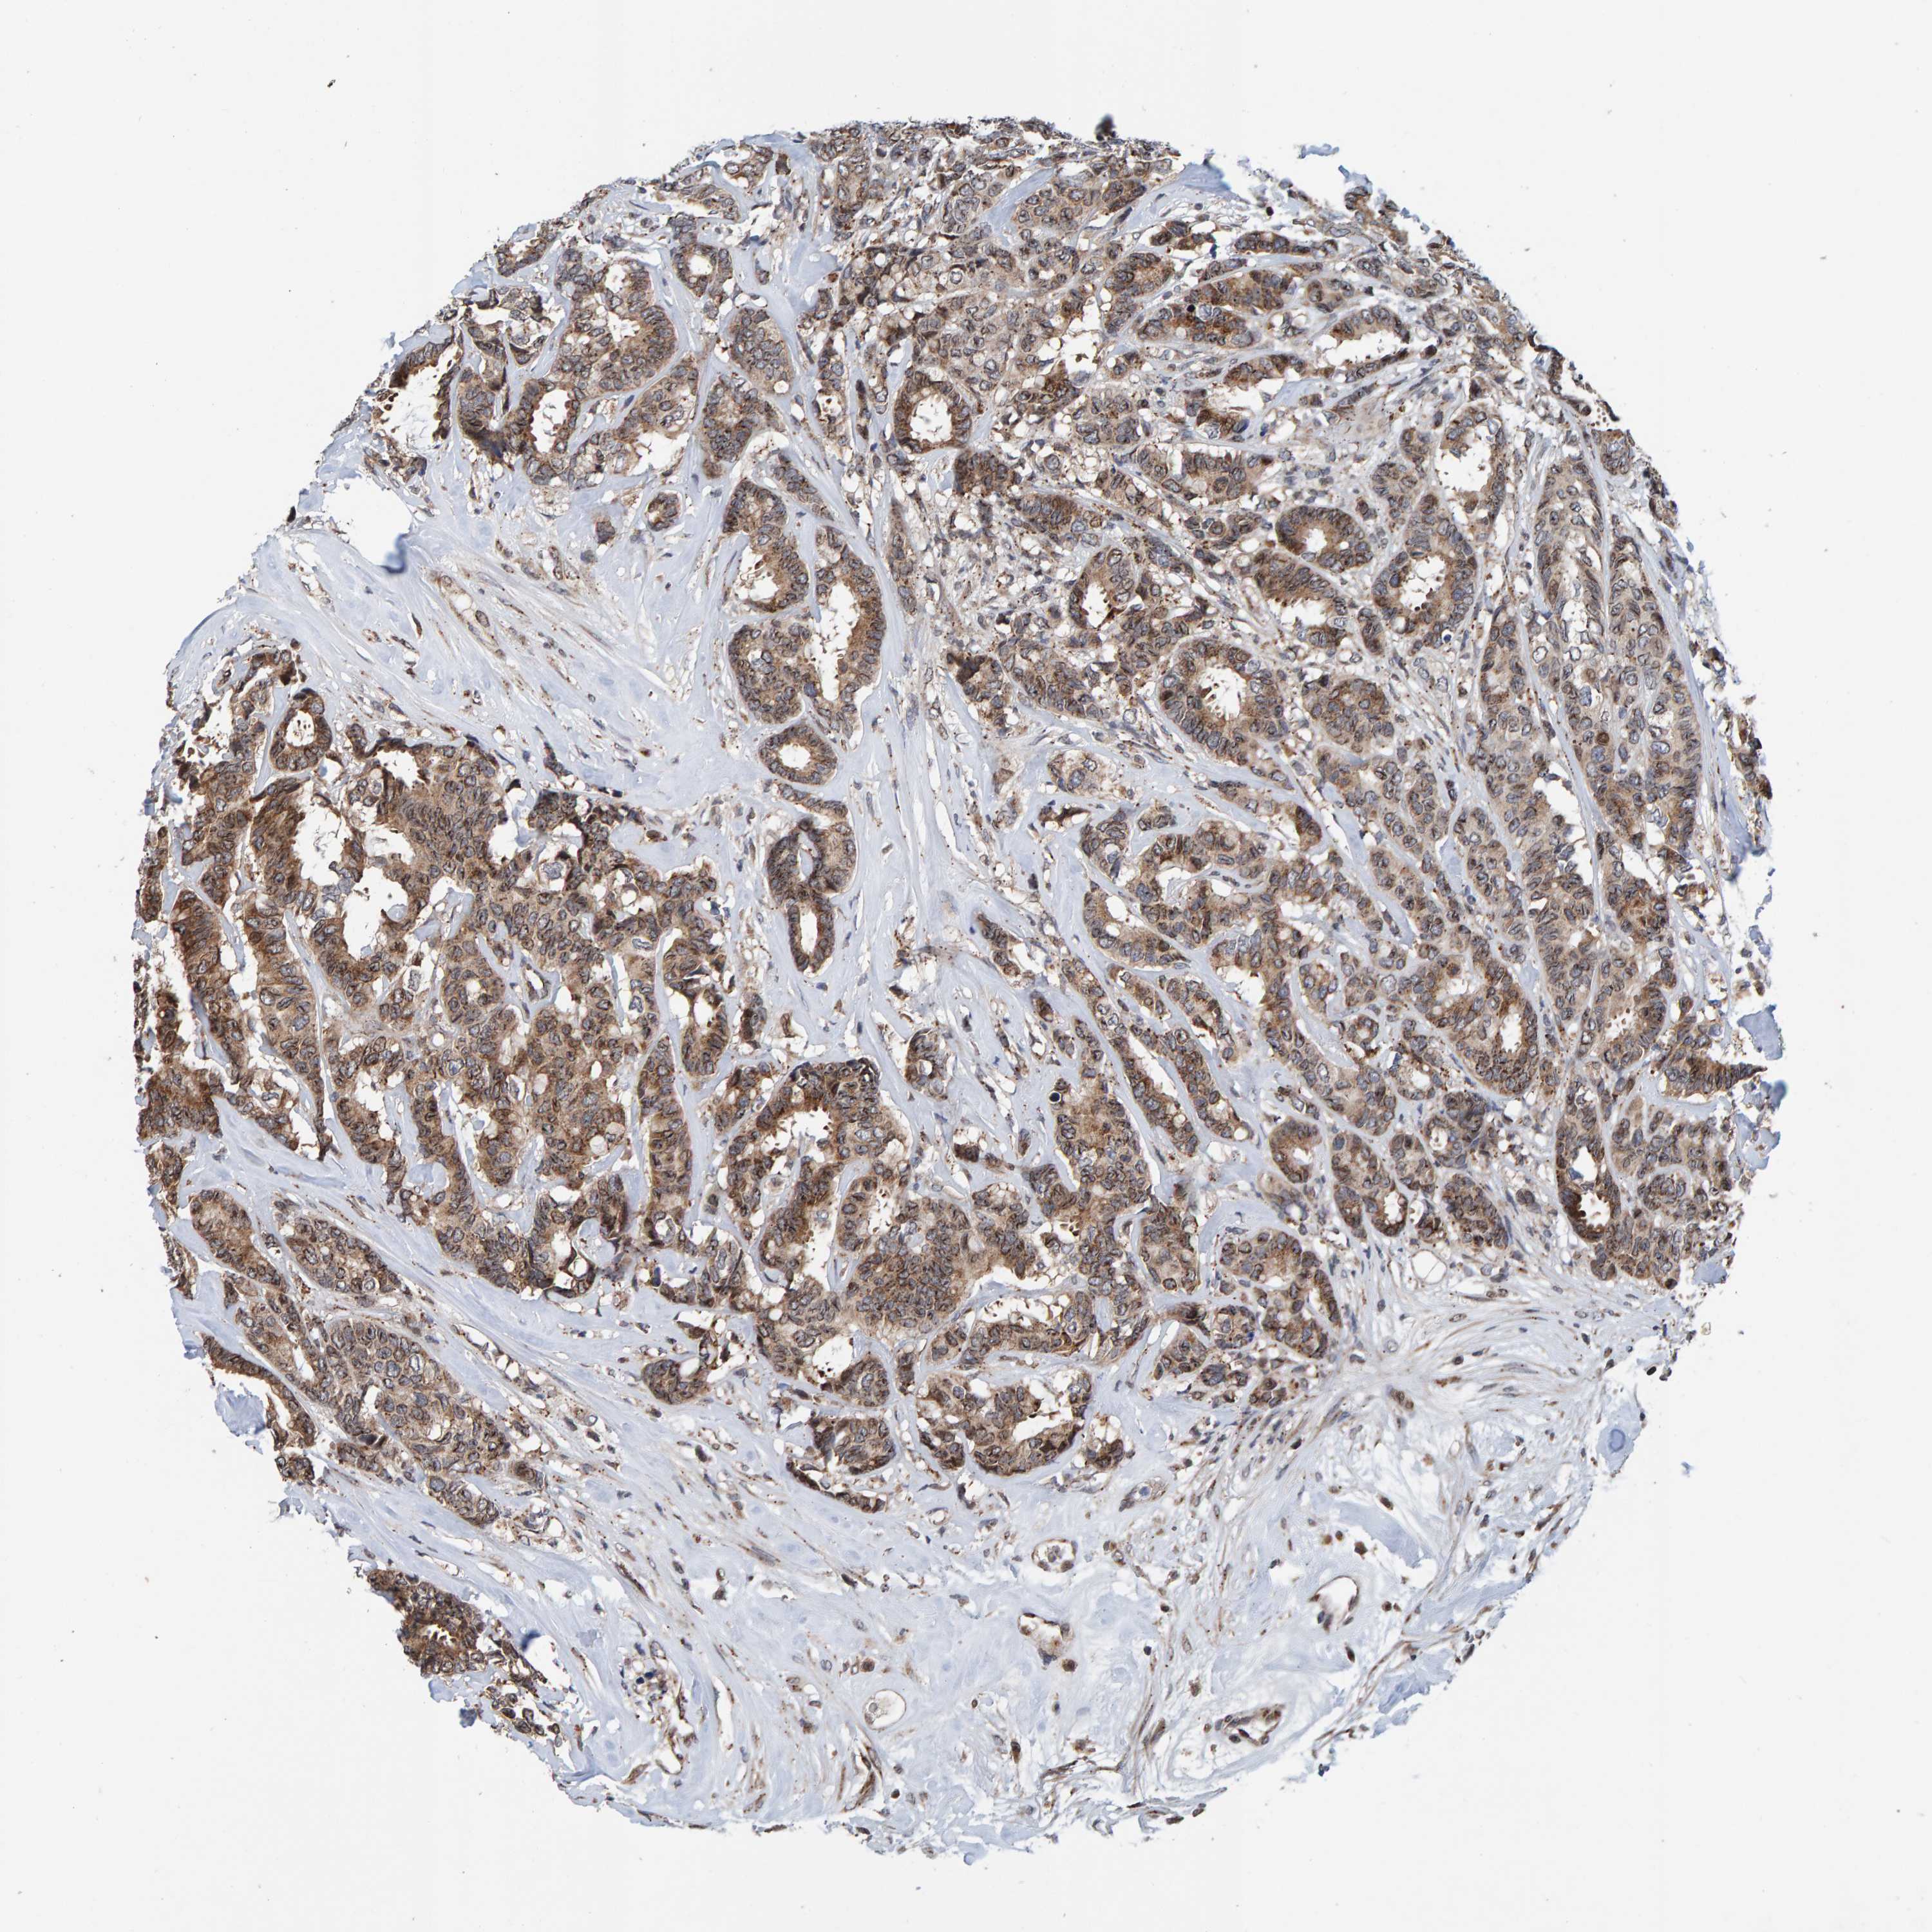

CANCER BREAST CANCER Show tissue menu

BRCA TCGA BRCA VALIDATION PROTEIN EXPRESSION